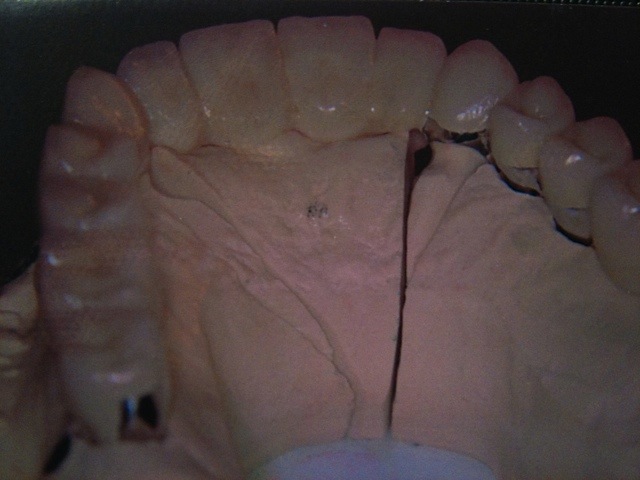

Implantation – Patientenbeispiel 1: